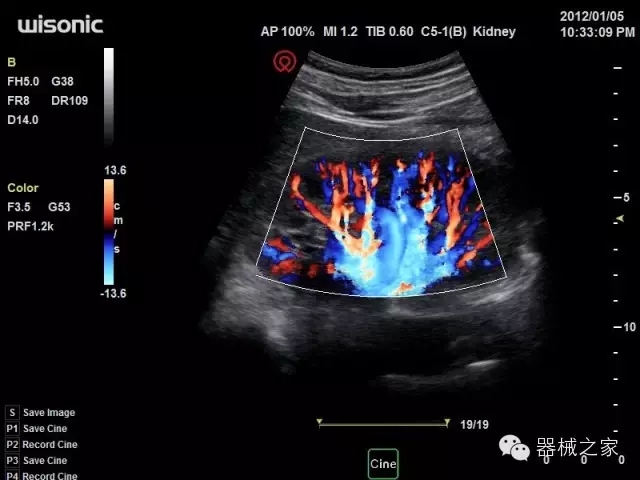

臨床圖片賞析

產(chǎn)品特點

·全球目前唯一一款配備主機雙探頭接口,整機重量(含電池)在5公斤以內(nèi)的便攜式彩超;

·獨有的HoloTM PW 實時3取樣門PW成像技術(shù),精確進行血管診斷;

·一鍵優(yōu)化B、Color、PW,Auto Doppler自動識別血管位置、偏轉(zhuǎn)角度等,提高工作效率;

·30°超廣角精細偏轉(zhuǎn)成像技術(shù),更優(yōu)異的頻譜圖像;